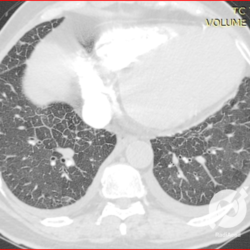

Opacidades em vidro fosco difusas com espessamento liso de septos e moderado derrame pleural bilateral.

Opacidades em vidro fosco difusas com espessamento liso de septos e pequeno derrame pleural bilateral.

Opacidades em vidro fosco, espessamento septal liso, proeminência de estruturas venosas e derrame pleural bilateral.